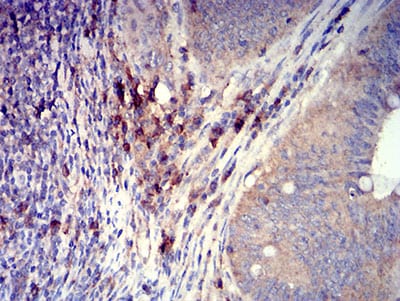

Product Image |

| IHC | 1/200 - 1/1000 |